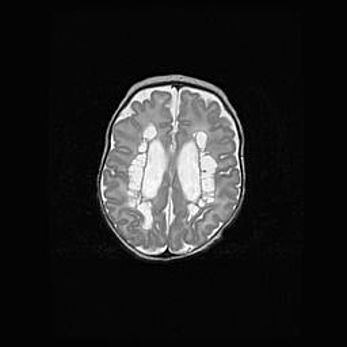

Множественные кисты обоих полушарий головного мозга, наибольшая из них в правой затылочной области. Ассиметричная атрофическая гидроцефалия.

Возраст: 7 месяцев

Вес: 5660 г

Пол: мужской

Окружность головы: 41,5 см

Срок гестации: 28-29 недель

Кисты головного мозга развиваются в результате многоочаговых некрозов вещества мозга и возникают вследствие перенесенной перинатальной инфекции, менингитов, энцефалитов, асфиксии, родовой травмы, расстройств мозгового кровообращения различного генеза. Образованию кист в веществе головного мозга плодов и новорожденных способствуют такие факторы, как высокое содержание в нем воды, недостаточная (или отсутствие) миелинизация и слабая астроглиальная реакция на повреждение.

Кисты могут сочетаться с гидроцефалией и другими поражениями головного мозга.